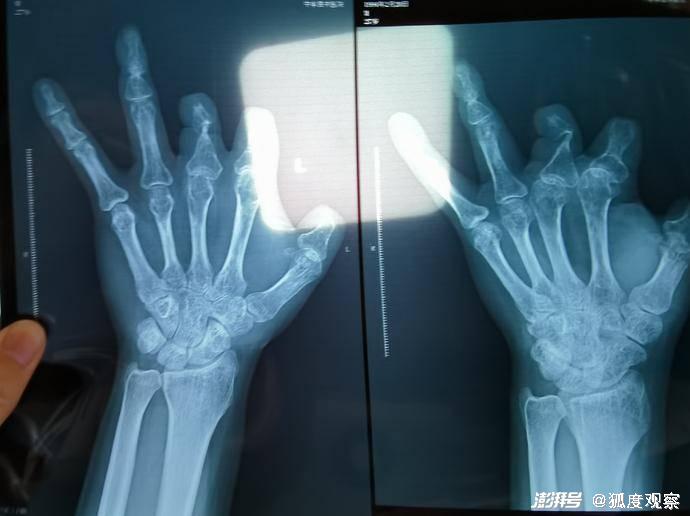

微血管吻合装置单价上万元,有时一台手术需要用几套,并且目前医保不予报销。这么大一笔医疗费用,患者当然会很在乎。该装置为植入型医用耗材,内有不锈钢针,X光拍片可以显影,这给事后监督提供了一种好办法。既然患者已被收取该装置的费用,术后拍片未发现体内有此装置,患者追问该装置去了哪,实属人之常情。

▲患者后期拍摄的X光片显示,未见一个微血管吻合装置。新京报记者 程亚龙 摄

这个偷梁换柱的典型案例,与微血管吻合装置去向不明有许多相似的情节,比如患者同样是通过术后进行X光拍片才发现疑点。对于可能出现的这类操作,监管显然应该保持警惕并加强防范。